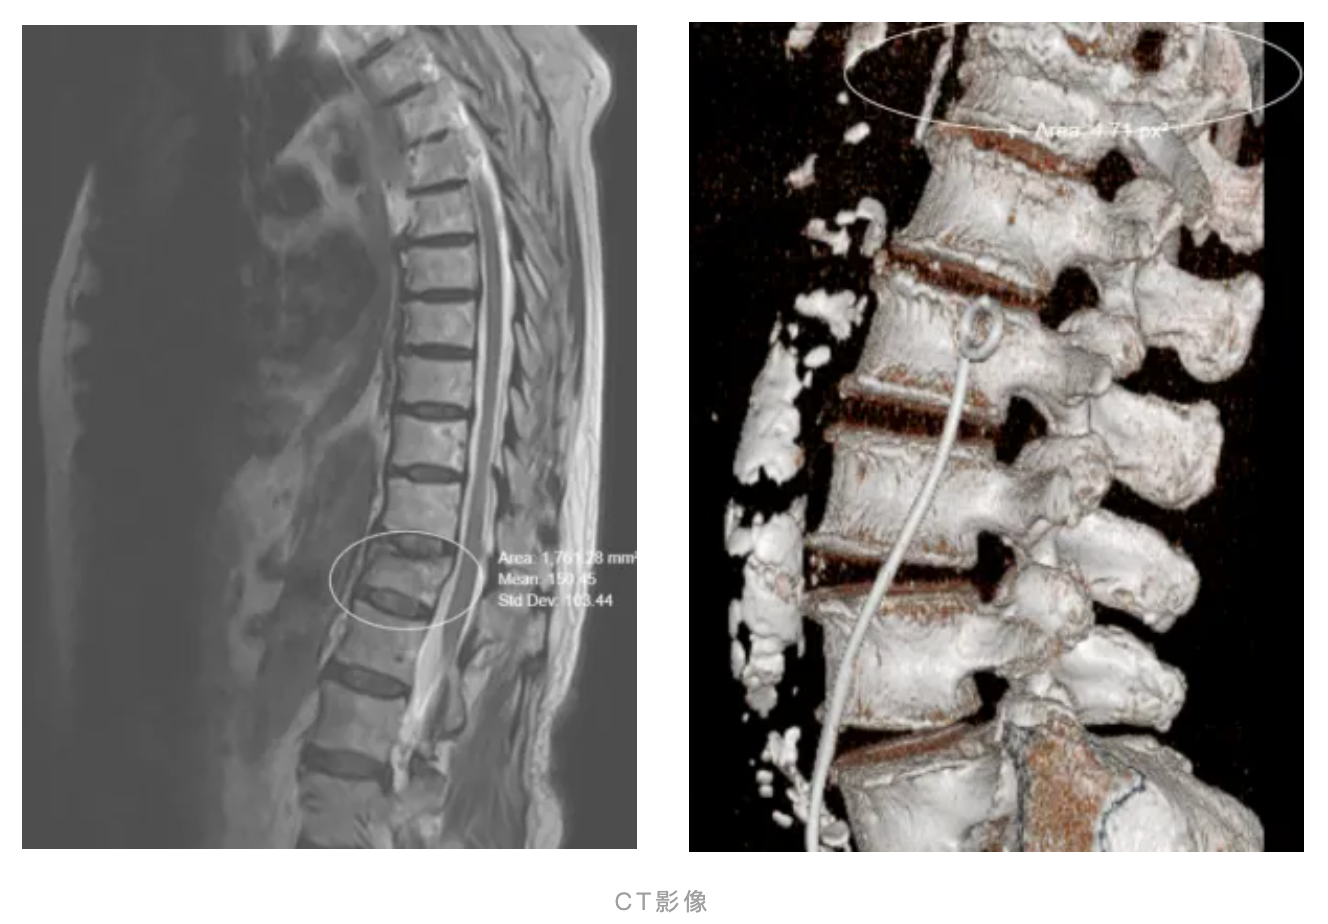

个体化方案是关键。李勤主任团队通过详细问诊,了解李奶奶的既往病史后,对李奶奶进行了详细的体格检查,辅助X光、CT及MRI等影像检查,考虑李奶奶既往有陈旧性胸椎骨折,伴有新发胸椎骨折。根据患者年龄、健康状态、骨折类型、神经损伤情况、骨质疏松及患者本人及家属诉求综合制定在局麻下行经皮椎体后凸成形术(PKP)。

经皮椎体后凸成形术(PKP):在影像引导下,向压缩的椎体内放置钛网、注入骨水泥,快速稳定骨折部位,恢复椎体高度,进而实现缓解疼痛。PKP有创伤小、恢复好的特点,特别针对李奶奶这类高龄体弱合并其他疾病患者。